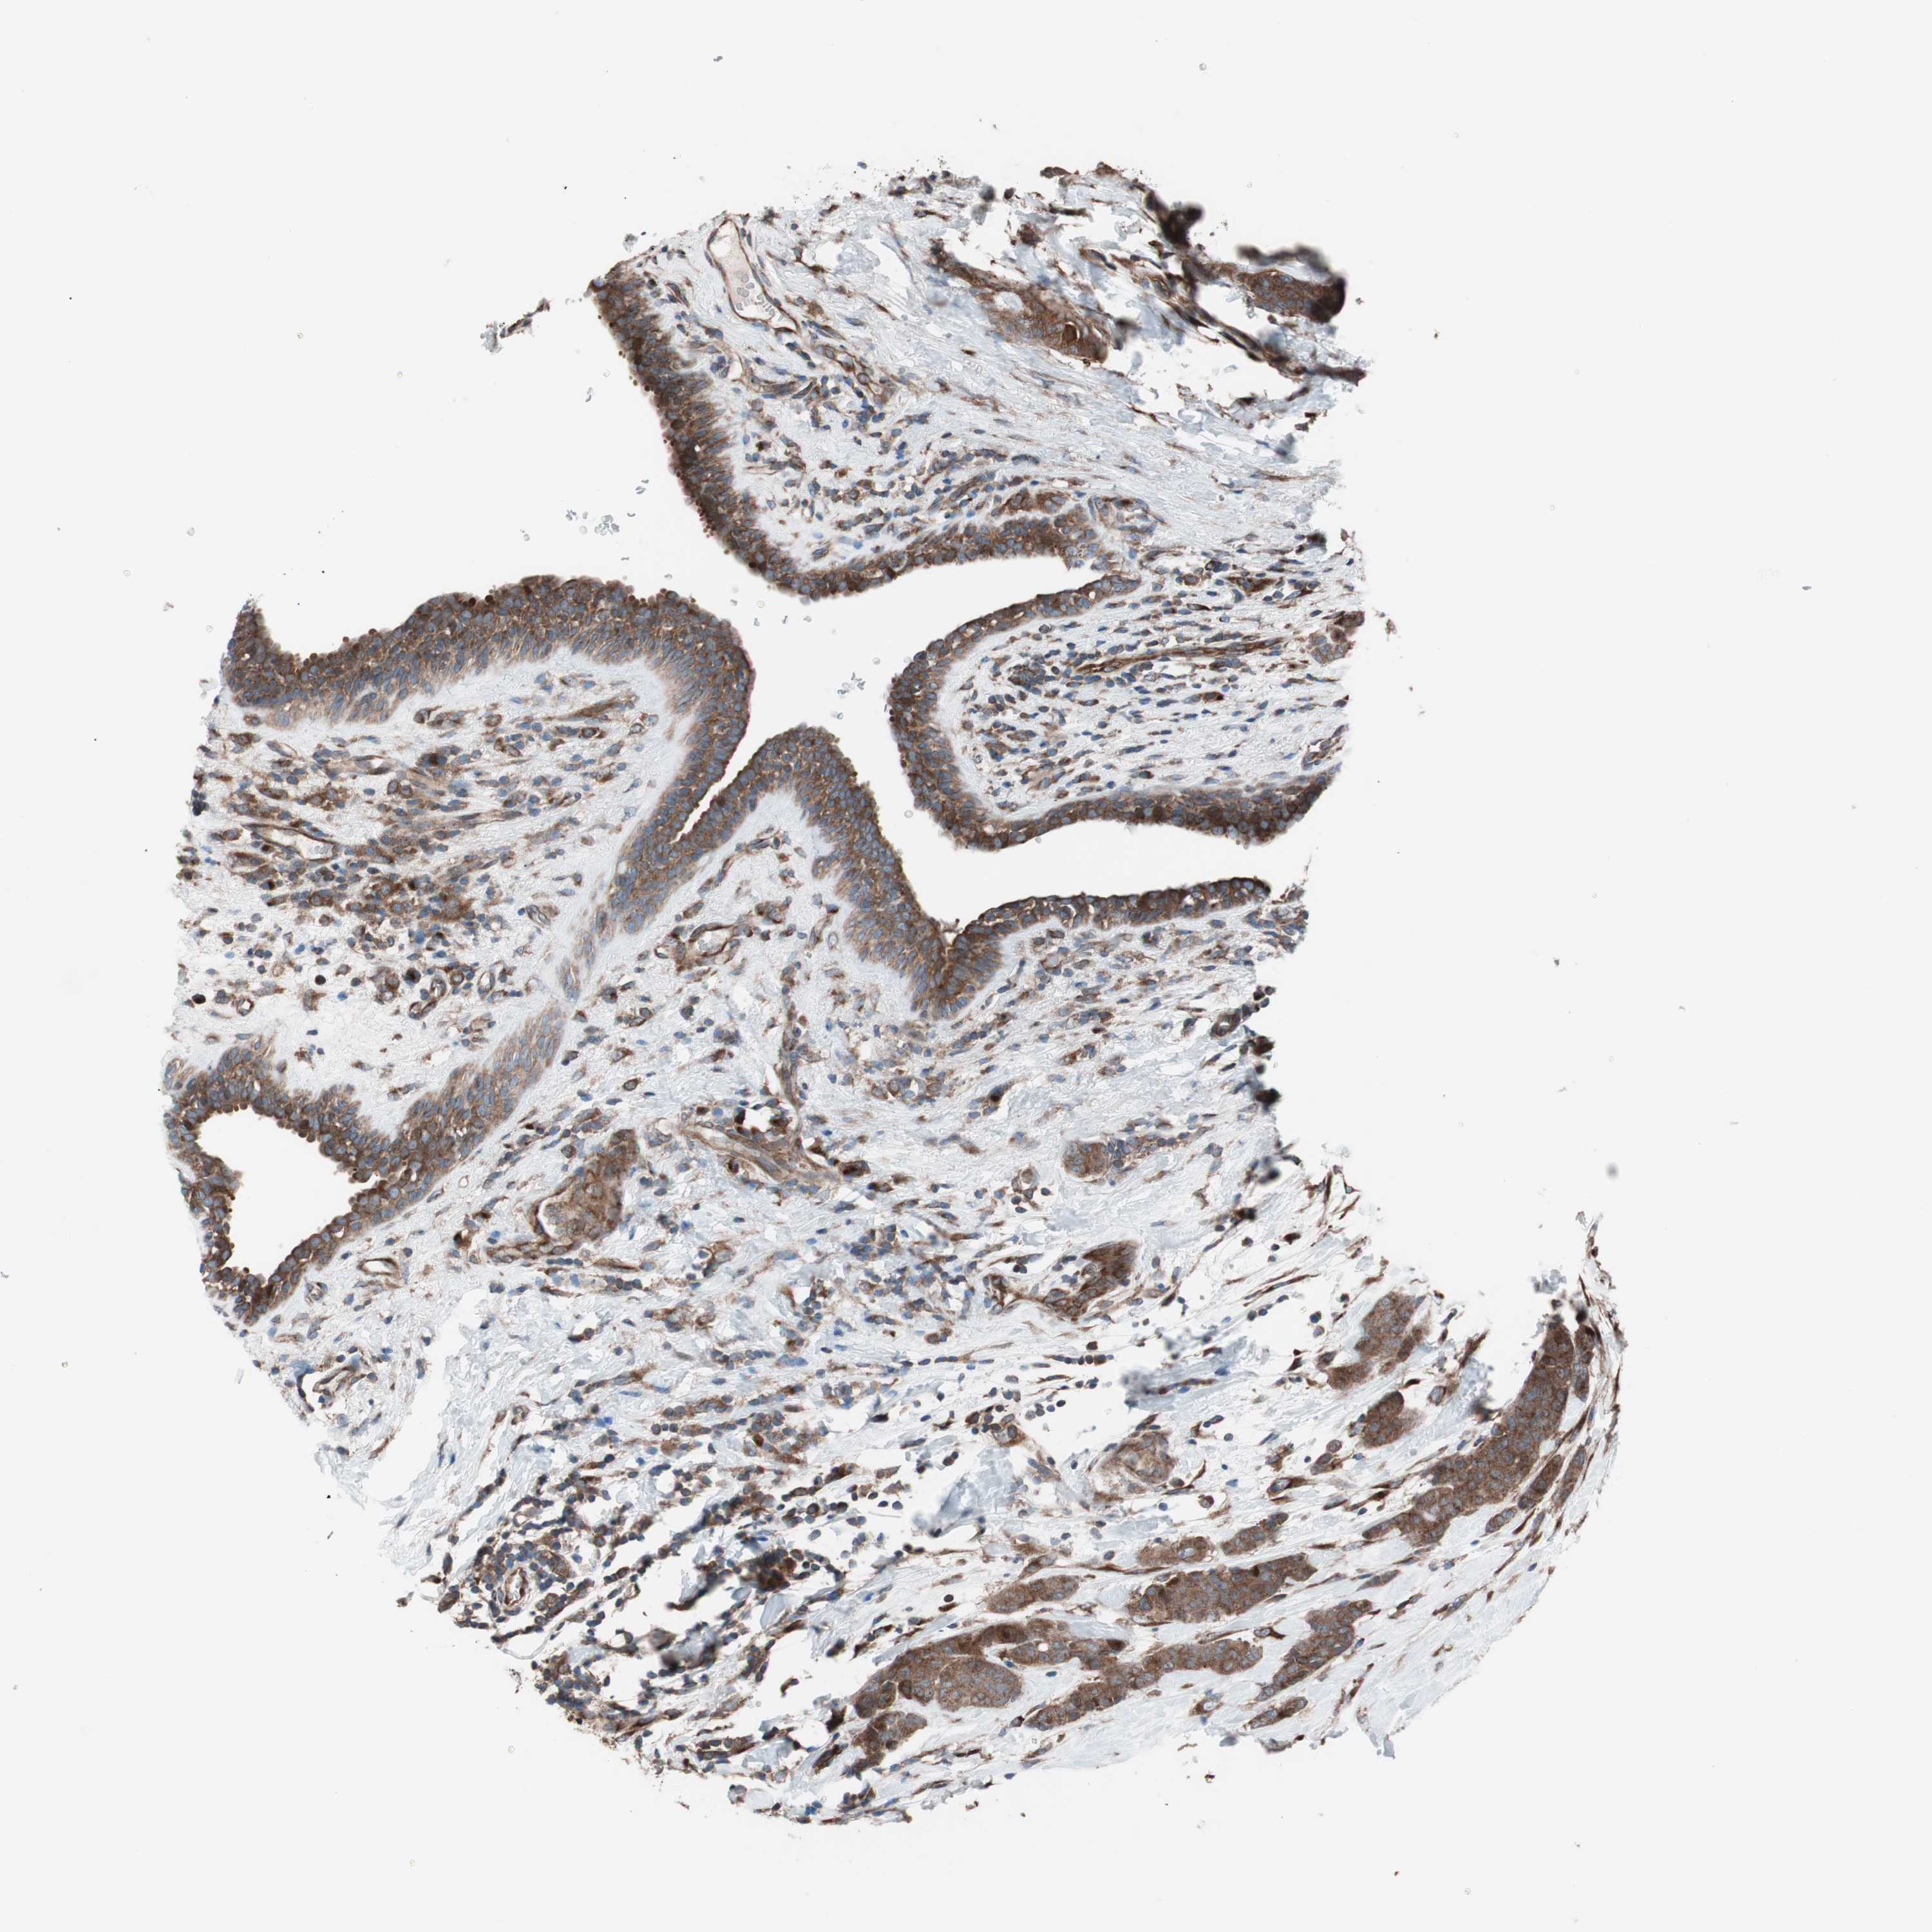

CANCER BREAST CANCER Show tissue menu

BRCA TCGA BRCA VALIDATION PROTEIN EXPRESSION